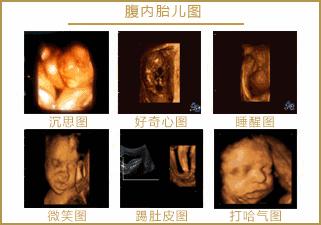

4 孕期超声一般会有六次

第一次超声检查:6-8周期间:

主要是观察是否为宫内孕,是单胎或多胎,是否有胎心,胎芽长度,主要为建档提供参考,需憋尿检查。

第二次超声检查:11-14周期间

主要为测量胎儿NT值。

第三次超声检查:22-24周期间

本次检查主要为检测胎儿是否患有重大畸形,主要是筛查出胎儿致死性畸形:无脑儿、严重脑膨出、严重开放性脊柱裂、单腔心等;

第四次超声检查:28-33周期间

晚孕期胎儿畸形筛查

第五次超声检查:36-38周期间

这个时候检查主要是了解胎儿生长发育情况,确定胎位、看胎儿大小、了解胎盘成熟度,看看羊水脐带的情况,进行产前的最后评估,为胎儿生产做好准备。

第六次超声检查:生产前最后检查